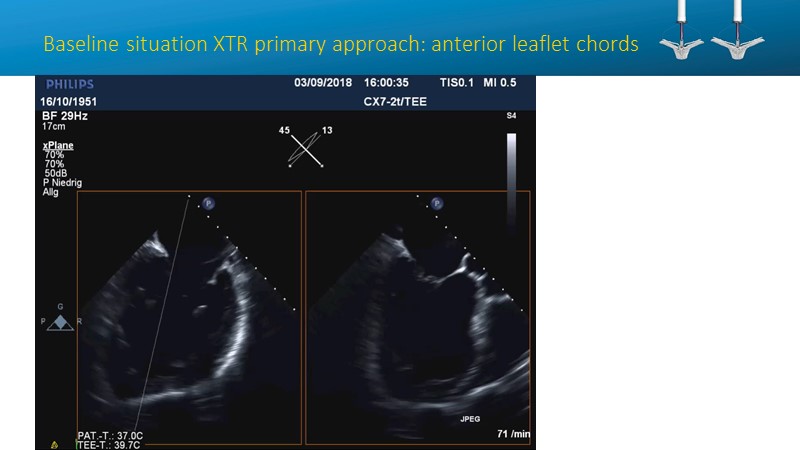

- To learn how will product innovation (Mitraclip NTR / XTR) drive improvement in procedural and clinical outcomes (EXPAND)